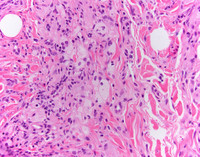

High power H&E

At higher power, foamy histocytes with bland nuclear morphology occurring singly and in aggregates are noted. These cells are characterized by vacuolated cytoplasm,  often in a fibrotic background with admixed chronic inflammation.